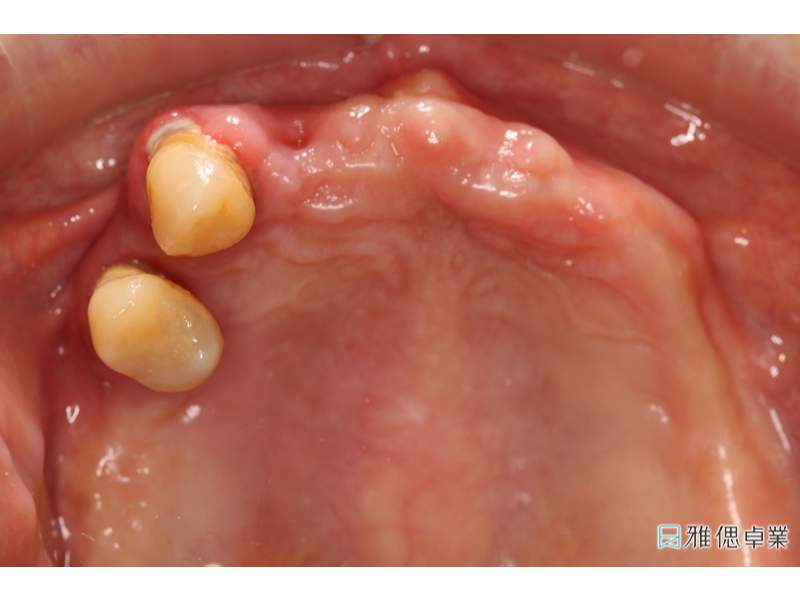

術前環口X光片,上顎只剩下2顆牙齒,下顎也有牙周、排列、咬合等問題

口內取定位模型

全口假牙模型,模擬自然牙支台齒